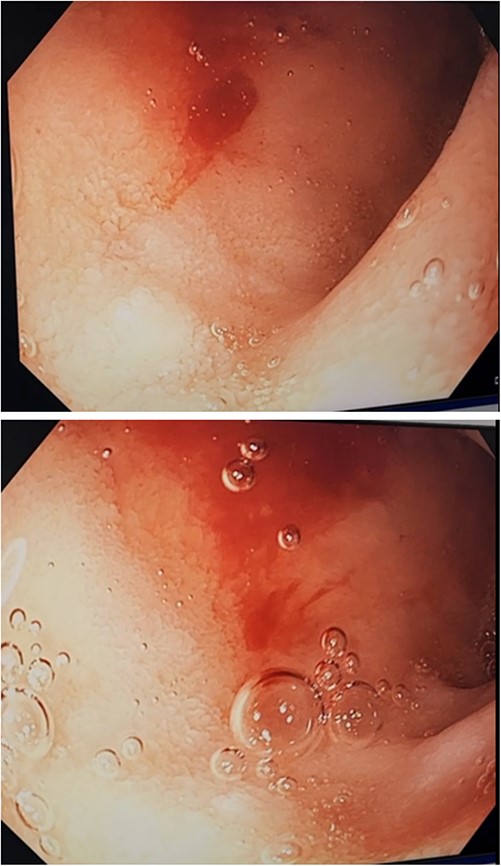

An 85-year-old female presented to hospital with melena and anaemia. She was functionally independent. Her past medical history included hypertension, and medications included irbesartan and low dose aspirin for primary cardiovascular prevention. She was haemodynamically stable with a haemoglobin of 75 g/L (previously normal) and urea of 21.9 mmol/L. CT-angiogram (CT-A) demonstrated no active contrast extravasation. She received two units of packed red blood cells (PRBCs), was commenced on intravenous pantoprazole, and underwent gastroscopy. This revealed a linear ulcer on the greater curvature of the stomach 5 cm from the gastroesophageal junction (GOJ) with an adherent clot and no active bleeding (Figs 1 and 2). The ulcer was injected with adrenaline and haemostasis achieved. The first and second part of the duodenum (D1, D2 respectively) appeared normal.

Initial gastroscopy - linear gastric ulcer on greater curvature of stomach.